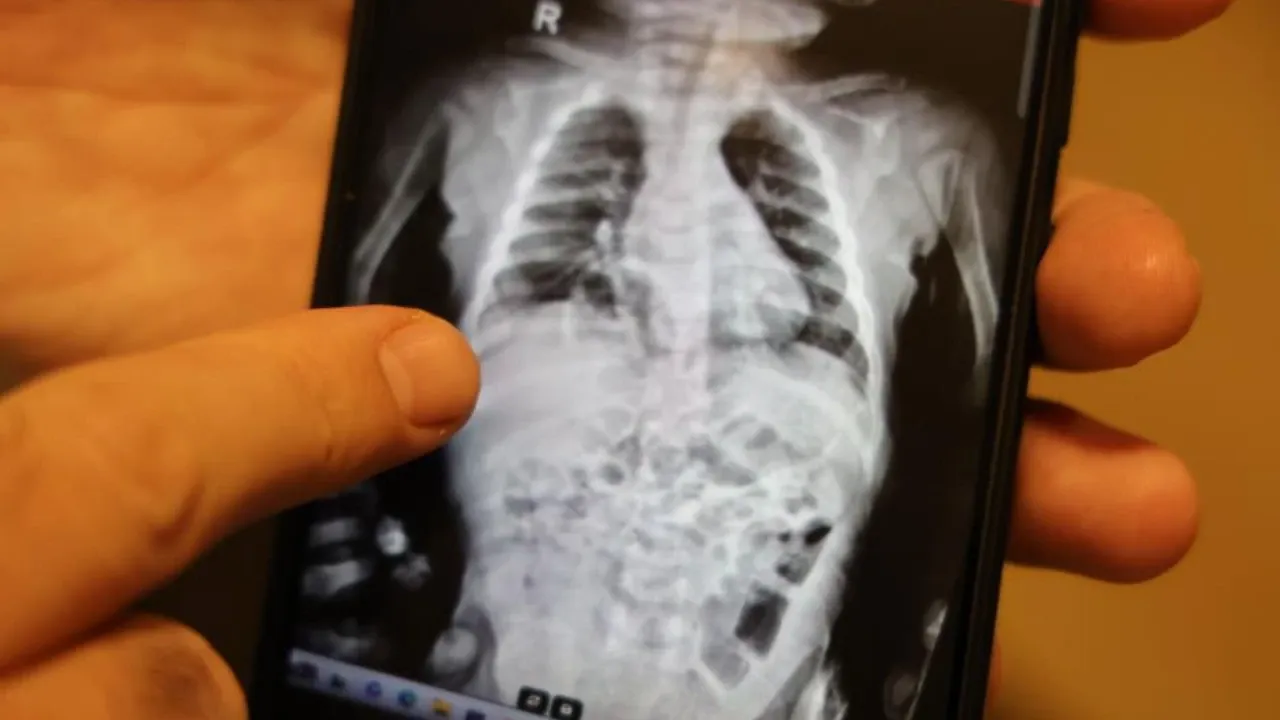

Burada yapılan ileri tetkiklerde, diyaframında doğuştan bir yırtık olduğu, bu nedenle bağırsakların göğüs boşluğuna çıkarak akciğeri baskı altına aldığı tespit edildi.

Operasyonu gerçekleştiren Çocuk Cerrahı Op. Dr. Taner Kamacı, hastalığın “Morgagni hernisi” adıyla bilinen, son derece nadir bir diyafram fıtığı türü olduğunu ifade etti.

“Yaklaşık 200 bin doğumda bir görülen çok nadir bir vakayla karşılaştık. Türkiye’deki doğum oranlarına göre, yılda yalnızca beş bebekte bu hastalık ortaya çıkıyor.

Hastamızın akciğer filmleri ve tomografik görüntüleriyle tanıyı kesinleştirdik. Operasyon sonrası durumu oldukça iyi seyrediyor.”